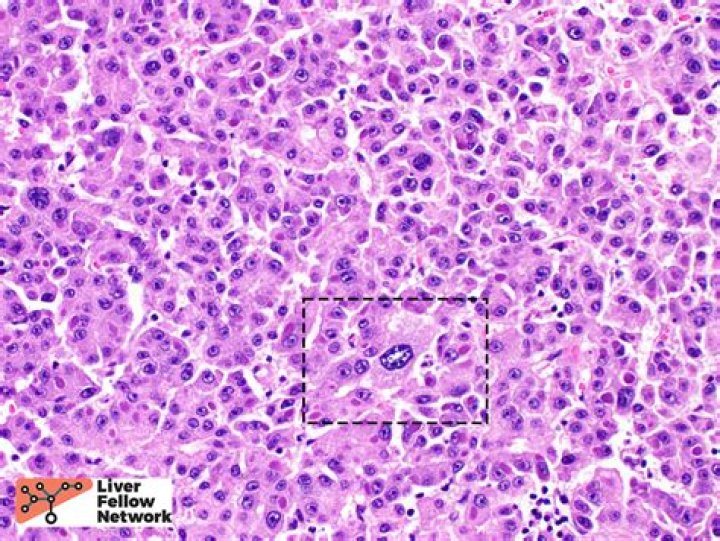

Can you survive hepatocellular carcinoma?

How bad is hepatocellular carcinoma?

Hepatocellular carcinoma is the most common form of liver cancer. It is a serious illness that can be life-threatening. If it diagnosed early, hepatocellular carcinoma can be treated with surgery to remove the cancerous tumor or with a liver transplant.